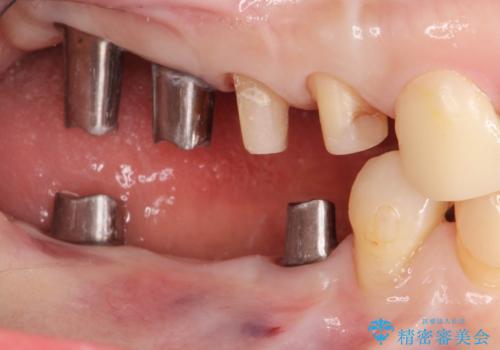

全顎 虫歯 インプラント治療

不適合やすり減ったクラウンを全て除去し、虫歯を丁寧に除去したのち精密なセラミック治療を行いました。

また失ってしまった奥歯についてはインプラントを用いて噛み合わせを確立する治療方針としました。